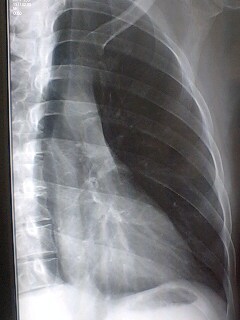

し・・・心臓に・・・

メイドさんが居たw

ってのは冗談で、整形外科の観点では健康だそうです。

脳外科行って来いって言われたので、また来週〜・・・。